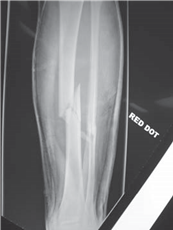

What do you see in these two radiographs?

T here is an AP view of the lower left leg showing multifragmented mid-shaft fractures of the tibia and fi bula, probably resulting from a high-energy impact. The chest radiograph suggests that there has been a signifi cant insult to the chest/lungs.

What do you understand by the term damage control orthopaedics (DCO)?

DCO is a planned and staged surgical strategy in the management of polytrauma patients to minimize the eff ects of the โ€˜second hitโ€™ on an already limited physiological reserve. The โ€˜fi rst hitโ€™ is from the injury and the bodyโ€™s response to this injury, while the โ€˜second hitโ€™ is produced by surgical intervention.

E vidence shows that, in certain patients, primary external fi xation of long bone fractures and secondary nailing improves outcome. There is a reduction in the incidence of multiple organ dysfunction syndrome (MODS) and adult respiratory distress syndrome (ARDS).

How do you decide which patients require DCO and what is the alternative?

The alternative way of managing polytrauma patients is known as early total care. This preceded the concept of DCO and involves the early treatment of all fractures. Patients who would be suitable for DCO include: those with Injury Severity Score > 20 with chest injury, those with abdominal or pelvic trauma in hypovolaemic shock (systolic blood pressure < 90 mmHg) and anyone with bilateral lung contusions.

What is the Injury Severity Score (ISS)?

T his is a scoring system based on the Abbreviated Injury Scale (AIS). Each body system is given an AIS of 1โ€“6 with 6 being the most serious. The ISS is calculated by adding the squares of the three most severely injured body systems. A patient with a score greater than 16 is defi ned as being seriously injured. In this case a patient would have greater than 10 % chance of mortality.

When do you expect to operate defi nitively on a DCO patient?

This decision will be made in conjunction with the anaesthetist and intensivist. I would usually expect this to be after at least 4 days. Parameters such as blood pressure, heart rate, arterial blood gases, and core temperature must be corrected to avoid the risk of a large second hit.

I would want to exchange from external fi xator to a nail within 10 days to avoid an increased risk of infection.